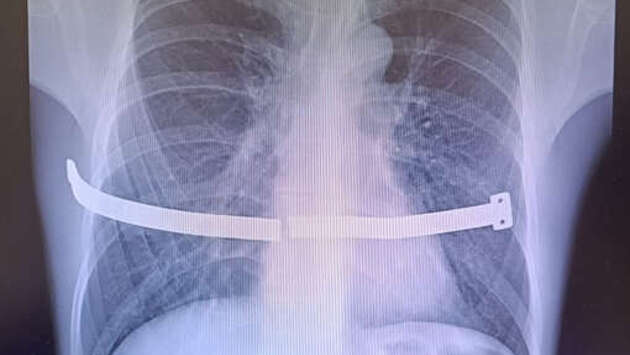

Врачи Сургутского травматологического центра спасли мужчину, беспечность которого едва не привела к серьезным повреждениям внутренних органов. Случаем из практики поделились в пресс-службе медицинского учреждения. Пациент 17 лет проходил с металлической пластиной в груди, которая, ожидаемо, раскололась, так как не была предназначена для столь долгой "эксплуатации". Конструкцию установили мужчине для коррекции воронкообразной деформации груди. Устройство следовало удалить спустя четыре года, но пациент не торопился с операцией. В итоге пластина разломилась пополам и один из ее краев стал упираться в оболочку сердца. Из-за сильных болей пациент обратился к медикам, и операции избежать не удалось. "Пациент все-таки расстался с пластиной. Хирурги успешно извлекли ее, несмотря на технические сложности. За многие годы металл уже сросся с костной тканью, пришлось частично резецировать ребро", - рассказали в пресс-службе, отметив, что это не повлияет на качество жизни. Медики отметили, что подобные вмешательства малотравматичны и мужчина зря подвергал себя рискам, отсрочивая ее.